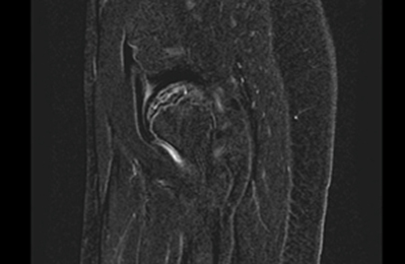

Post-Processing: Perform manual subtractions of the coronal and sagittal T1 Fat Sat sequences – postcontrast – precontrast = subtracted image. It should look like this: